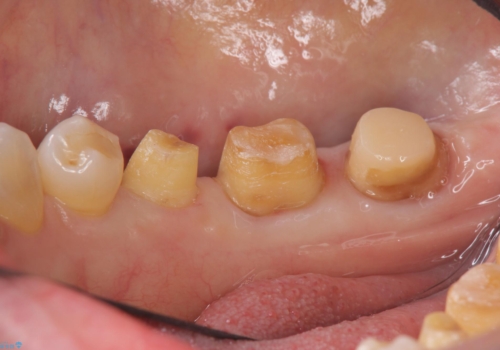

- 右下奥歯(7番)の高さがなく、かぶせ物(クラウン)にするためにあらかじめ歯周外科手術を行いました。(クラウンレングスニング)

右下5番は歯ぐき付近までWSD(くさび状欠損)で削れていたため、患者様と相談してクラウンにしました。その際、削れていたのが歯肉縁下に及んでいたため、一緒に手術範囲に含めました。

特に根尖に症状がなかったため、右下7番の根管治療はやり直していません。